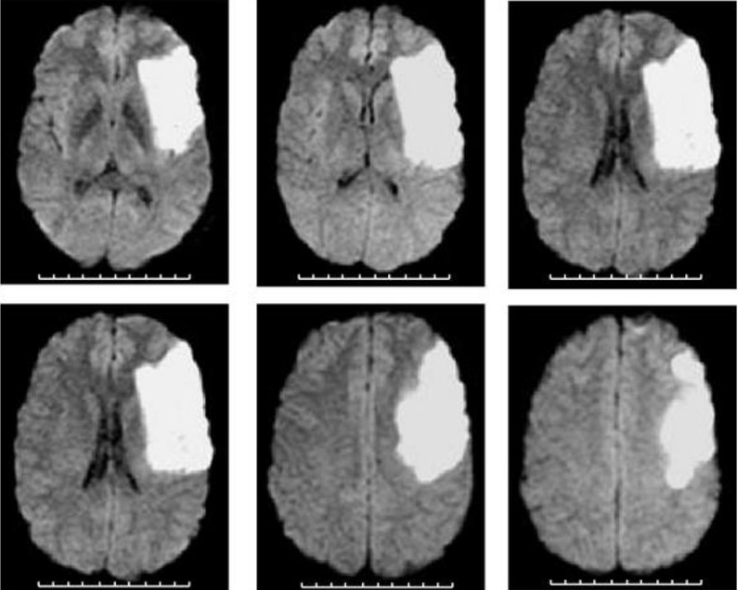

Basal Ganglia Stroke

ACA Stroke

MCA Stroke

PCA Stroke

• Different strokes affect distinct brain areas depending on the artery involved.

• Early recognition of symptoms is crucial for timely intervention.

• Understanding the arteries helps predict outcomes and guide treatment.